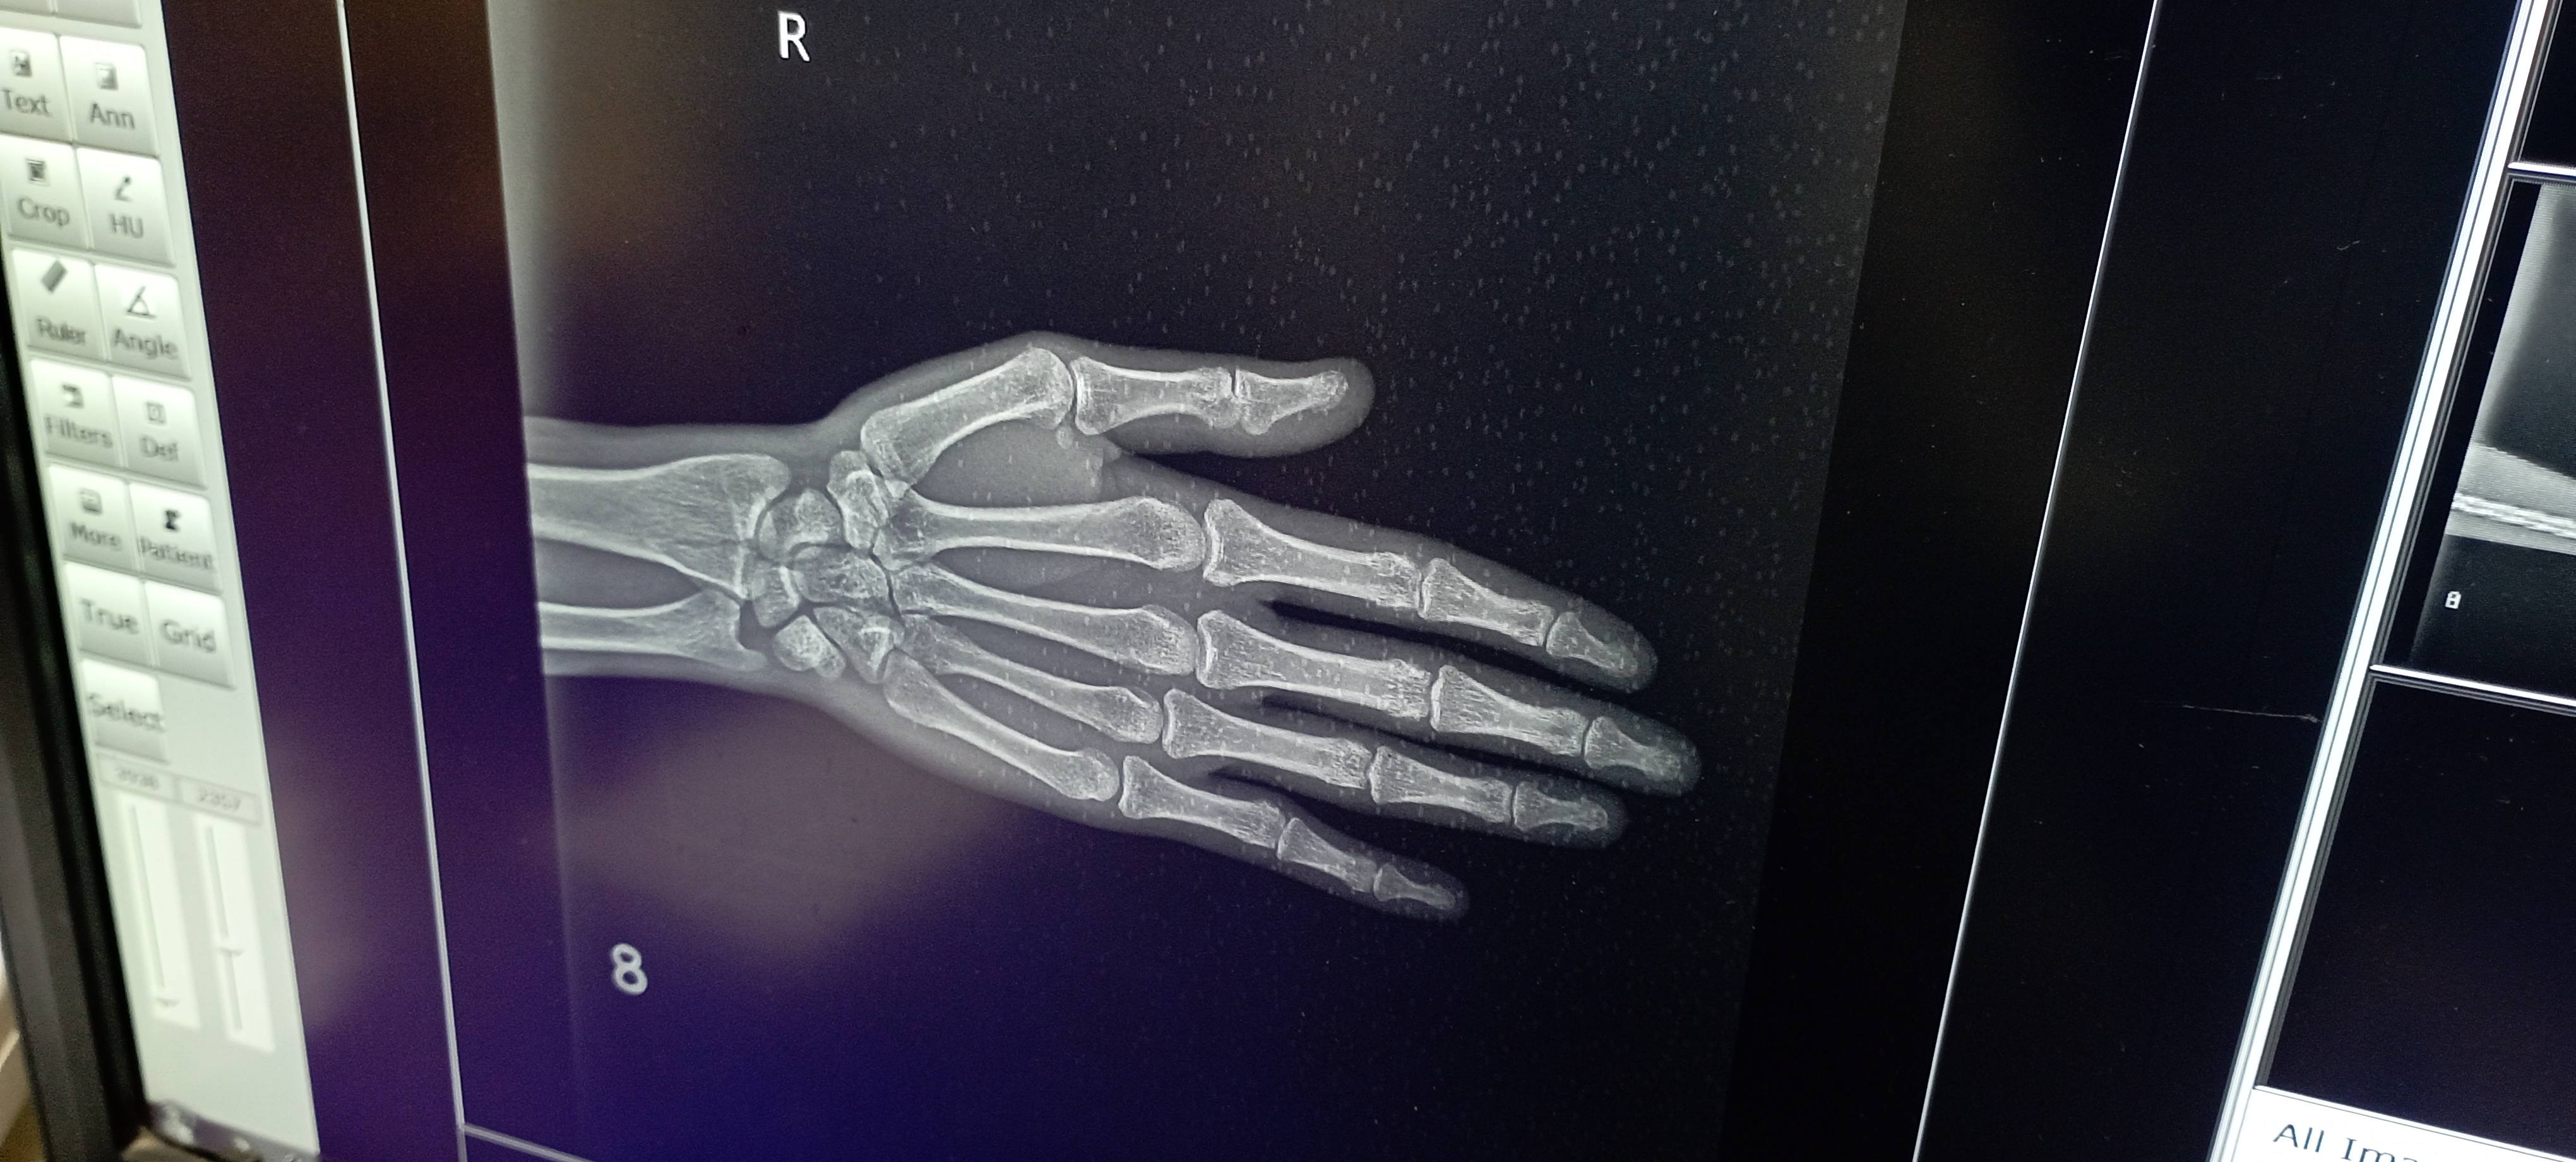

Sir mai 26 sal ka hu,,, mujhe ek dr ne wrist me normal fracture btaya aur ek orthopedic surgeon Dr ne operation krna pdega bol rhe the lekin mere hat me moment Thik chl rhi lekin thoda hat mudne me problem aa rhi aur weight bhi dhire dhire utha pa rha hu ,,, pls sir kuch solution btayi kya kru ? ?,,, qki aage mera physical test bhi aa rha hai.